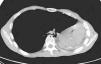

A los 2 meses de la aparición de los síntomas se procedió a la colocación por broncoscopia rígida de una prótesis metálica autoexpandible no recubierta (de 10mm de diámetro por 20mm de longitud) en el bronquio intermediario. A las 24h del procedimiento el paciente presentó remisión completa de los síntomas, incluso del dolor pleurítico. Durante los 6 meses siguientes la evolución ha sido favorable, sin que se hayan apreciado signos clínicos ni tomográficos de complicaciones (fig. 2). En la fibrobroncoscopia se observa la luz permeable del bronquio intermediario, con leve compresión extrínseca de la prótesis y la formación de pequeños granulomas que no han progresado en los últimos 3 meses.

Tratamiento endoscópico del síndrome posneumonectomía izquierda. En la tomografía computarizada de tórax efectuada a los 6 meses de la colocación endoscópica de una prótesis metálica autoexpandible en el bronquio intermediario (asterisco), tras neumonectomía izquierda y síndrome posneumonectomía, se observa el bronquio intermediario permeable, con un incremento de calibre de la luz bronquial si se compara con la figura 1.